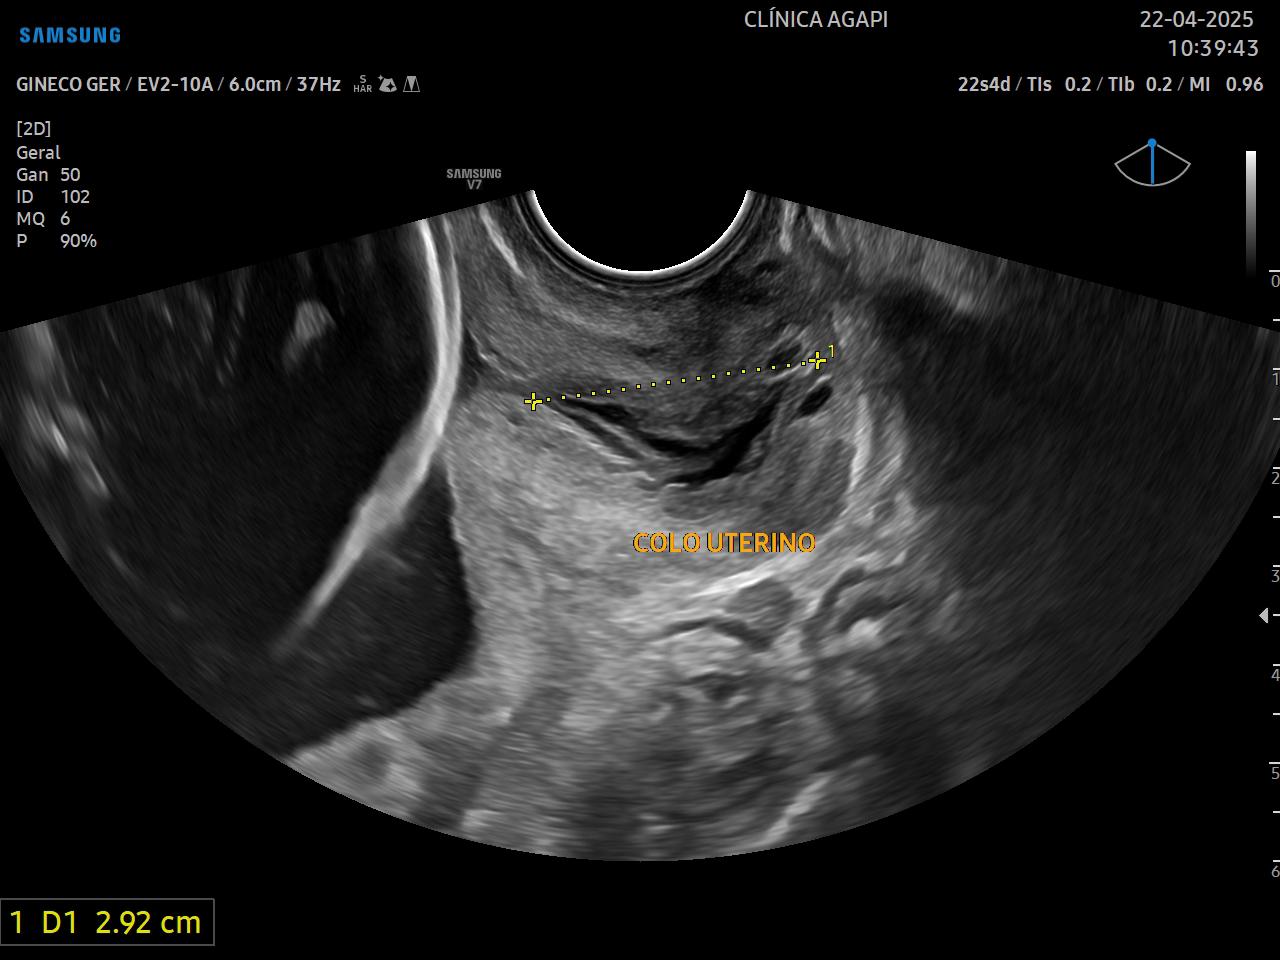

Além da análise fetal, também avaliamos a placenta, líquido amniótico e peso. Recomenda-se neste período a medida do colo uterino pela via transvaginal para avaliação de risco de prematuridade.